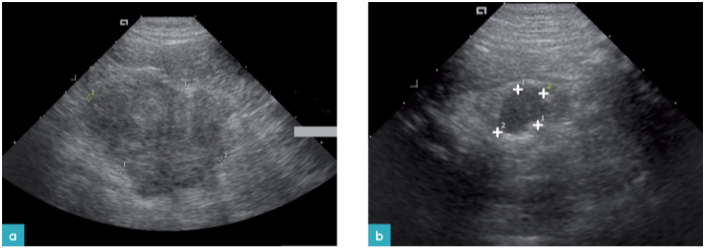

胰腺腺癌是最常见的胰腺肿瘤,也曾有文献报道过胰腺肉瘤。其他类型胰腺肿瘤包括腺瘤,鳞状上皮细胞癌,淋巴瘤,淋巴肉瘤,恶性肉瘤。肿瘤的典型超声表现为低回声团块或结节,较少情况下,会发现混合回声及钙化中心(图.16)。在胰腺腺瘤和胰腺腺癌的病例中,胰腺整体增厚,边缘不规则同时在实质内有多量低回声结节。

一例患有胰腺腺癌的猫仅发现存在胰管扩张,另一个患有淋巴肉瘤的猫胰腺超声表现正常。腺癌经常会转移到肝脏。胰腺淋巴瘤会广泛性地浸润胰腺实质(图17.视频4)。